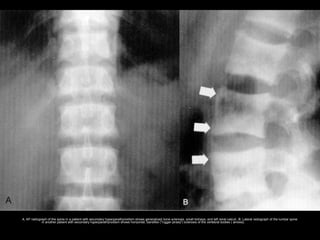

• Fractures - vertebral deformities, which

are also common, include biconcave

end plates (fish vertebrae) and anterior

wedging.

Lateral radiograph of the lumbar spine in a 55-year-old woman with postmenopausal osteoporosis shows generalized osteopenia,

compression fractures, and biconcave vertebral endplates ("fish vertebra"). Notice thin, well-defined vertebral cortices ( arrows).